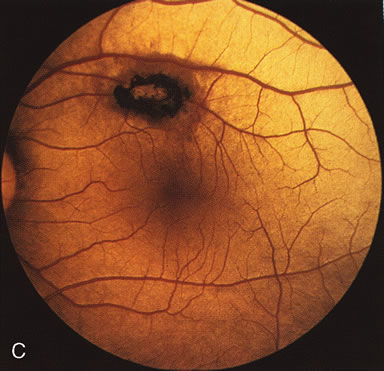

Fig. 1. Retinitis pigmentosa. A. A typical area of bone spicule pigmentation. B. Diffuse dye leakage is apparent throughout the posterior pole. C. The early angiogram shows dilated and irregular retinal radial peripapillary capillaries and perifoveal retinal capillaries. D. Leakage from these vessels are evident in the late angiogram.

Of more clinical importance is the role of FA in the diagnosis and treatment of cystoid macular edema (CME) (Fig. 1C and D). Stereoscopic FA indicates that the leakage, which may be diffuse or have the typical petaloid stellate appearance of CME, can come from the perifoveal retinal capillaries, from the choroid through the RPE, or from a combination of both sources.4 With the recent suggestion that CME in RP may be successfully treated with acetazolamide,5, 6 FA is thus important to document the diagnosis of CME, establish the origin(s) of leakage, and follow patients during and after therapy.